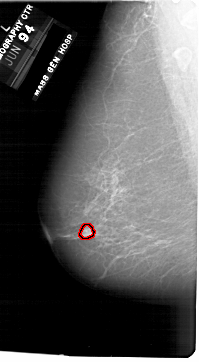

A_1750_1.LEFT_MLO

FILE: A_1750_1.LEFT_MLO.OVERLAY

TOTAL_ABNORMALITIES 1

ABNORMALITY 1

LESION_TYPE MASS SHAPE ROUND MARGINS CIRCUMSCRIBED

ASSESSMENT 3

SUBTLETY 4

PATHOLOGY BENIGN

TOTAL_OUTLINES 1

BOUNDARY